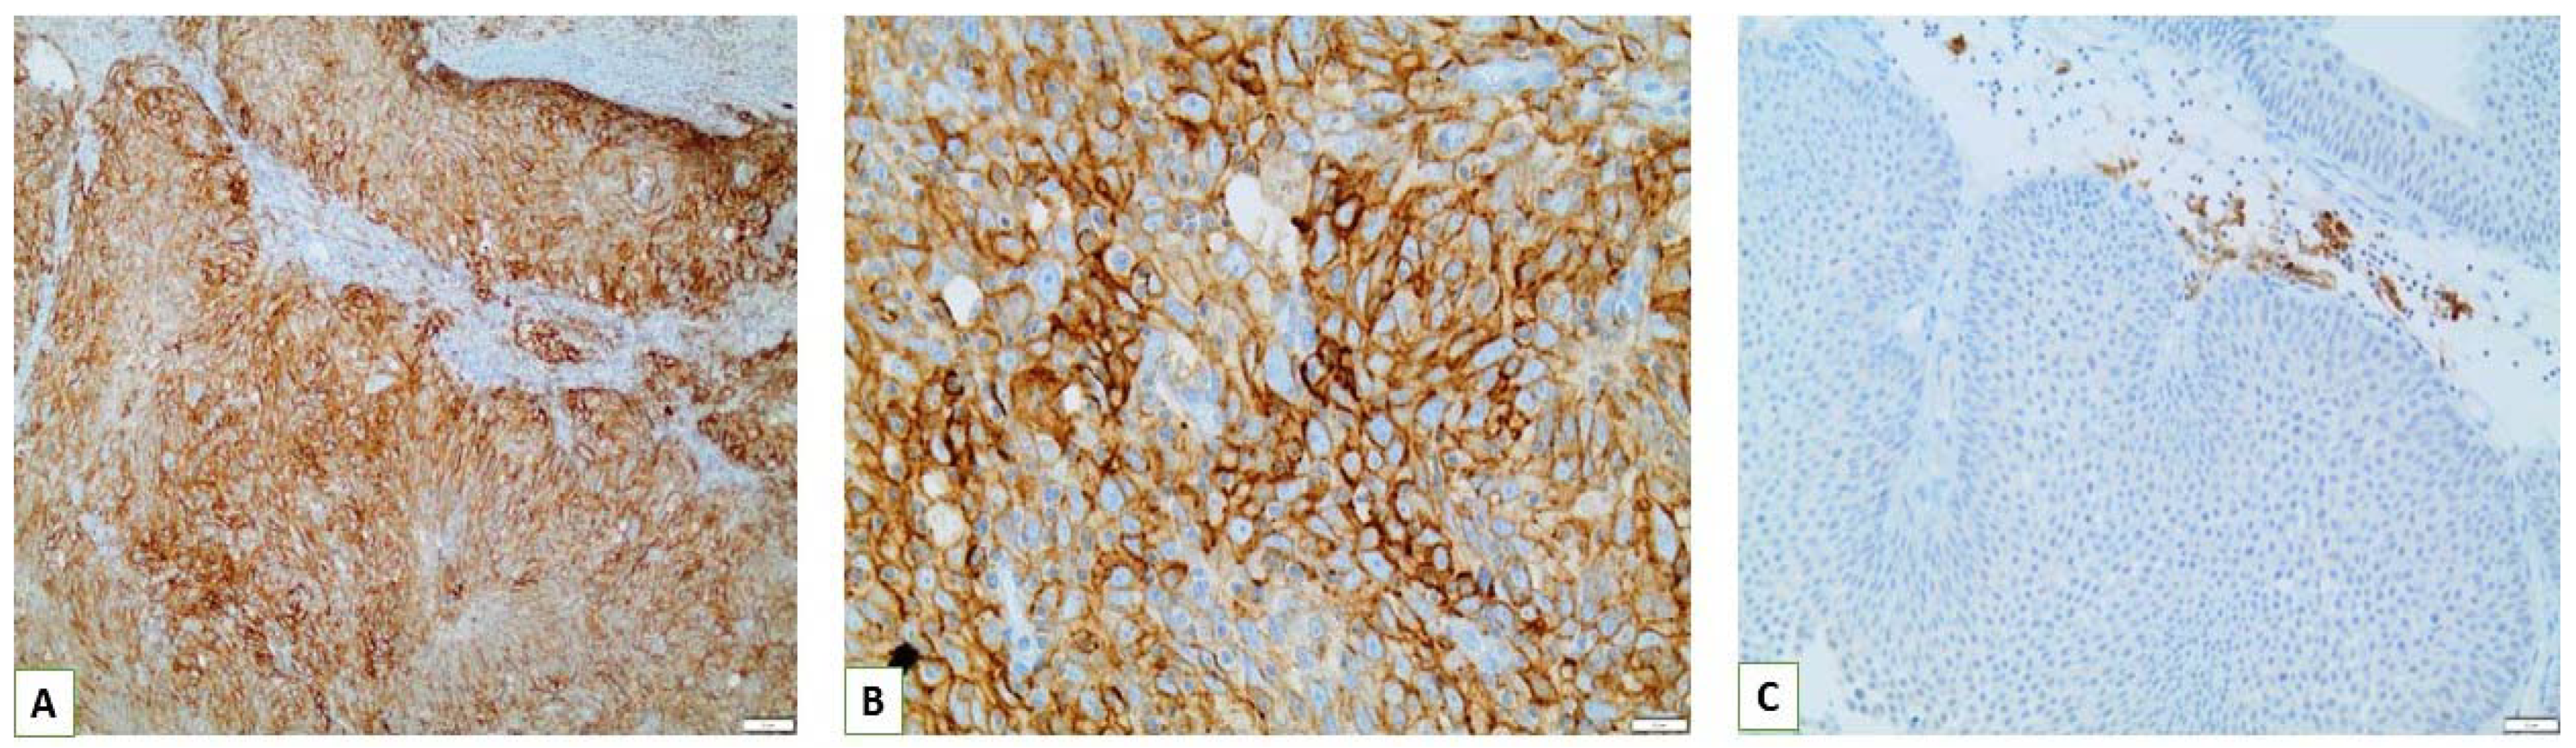

3.3. PD-L1 Assessment